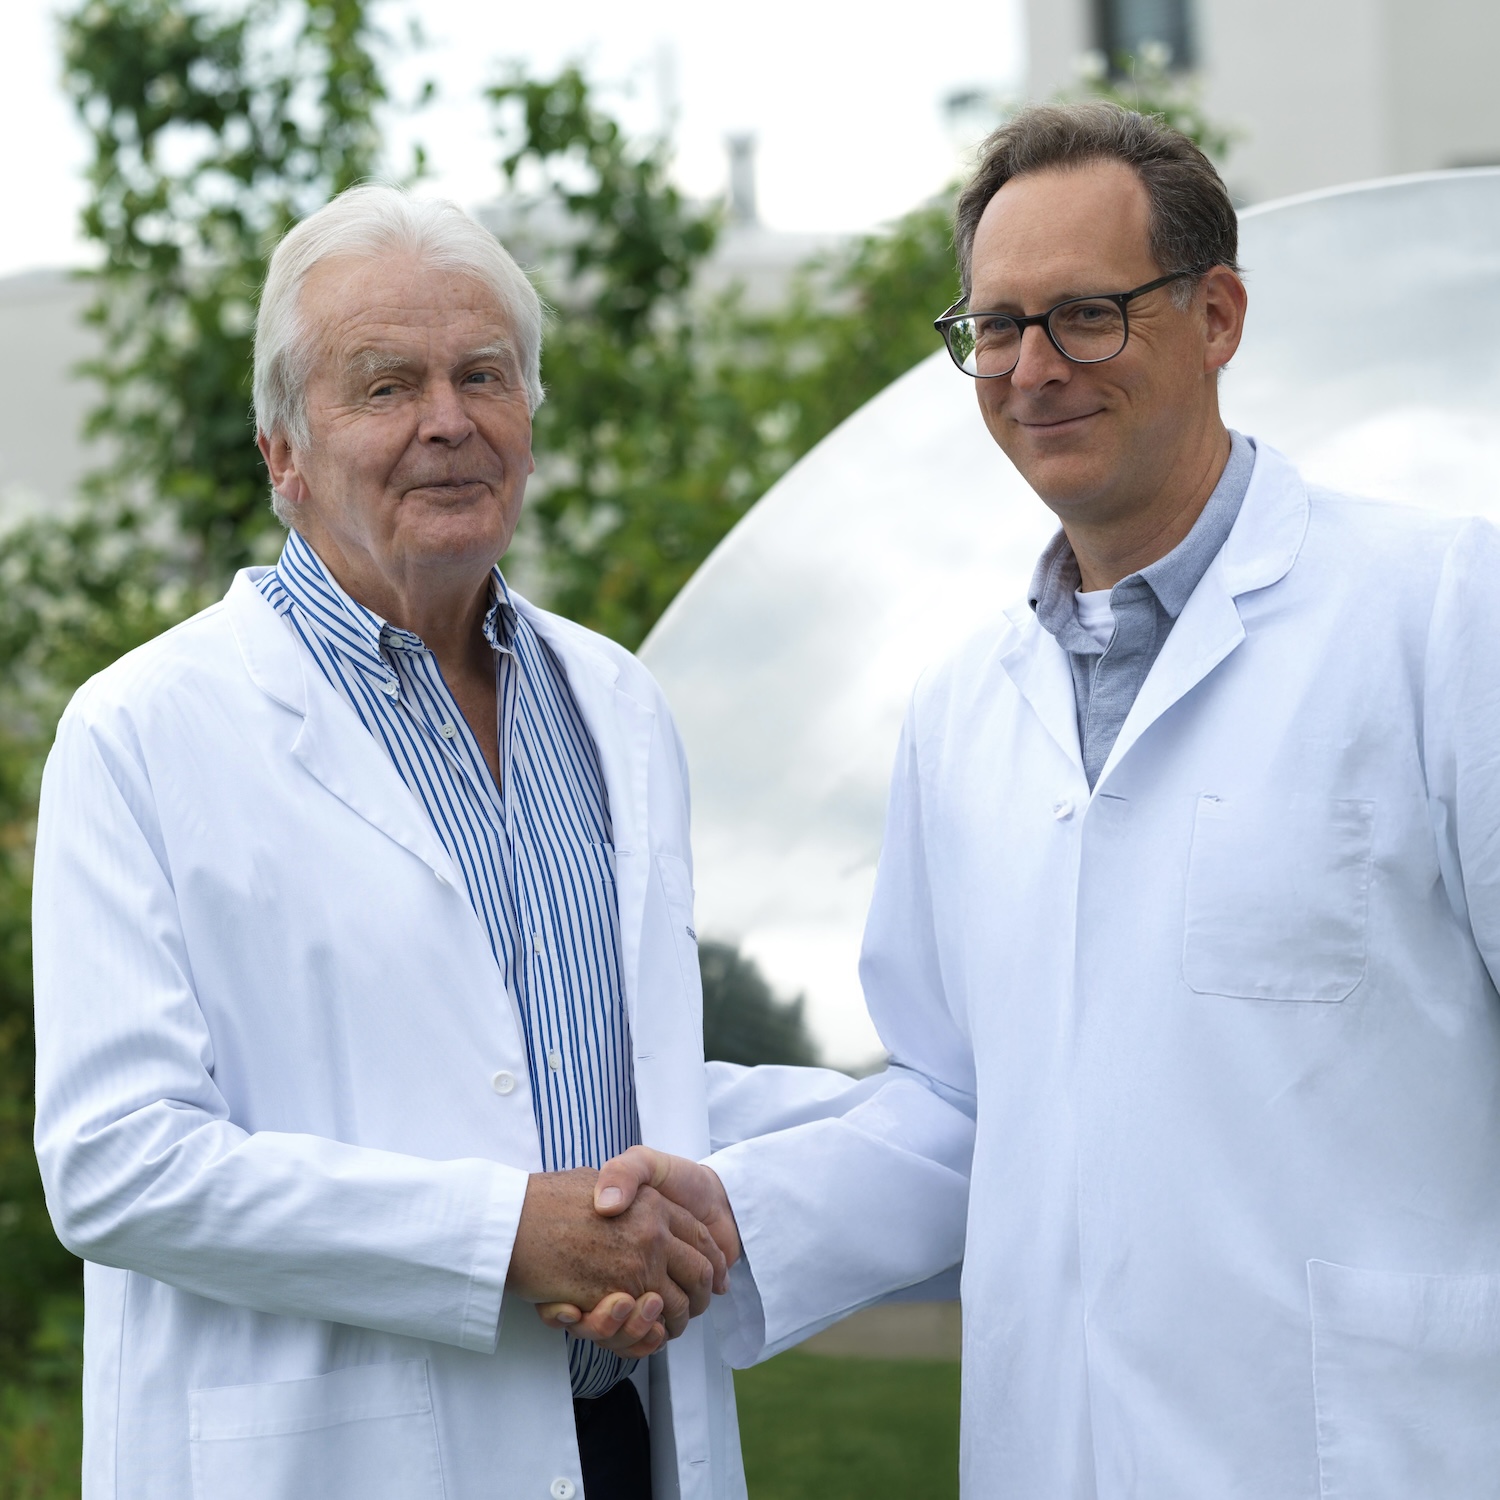

PD Dr. Rahm zählt national zu den ersten Anwendern des Keramik-Keramik Hip Resurfacing. Die innovative Prothese deckt lediglich die Oberfläche von Hüftkopf und Pfanne mit einer Keramikoberfläche ab.

Aufgrund der Beschaffenheit des Materials entsteht praktisch kein Materialabrieb, was sich sehr günstig auf die Langlebigkeit der Prothese auswirkt. Insbesondere für sportliche Patienten ist dies ein Lichtblick für die operative Behandlung einer Hüftarthrose.

PD Dr. Rahm wird ausführlich die Vor- und Nachteile dieser neuen Prothesenart vorstellen – oder gibt es sogar gar keine Nachteile mehr?

Dr. Philipp Neidenbach berichtet über die Entwicklung der Endoprothetik des Hüfgelenkes. Die Hüfttotalendoprothese revolutionierte seit den 1960er-Jahren die Behandlung der schweren Hüftarthrose, so dass die Implantation der Hüftprothese bereits 2007 als «Operation des Jahrhunderts» gefeiert wurde. Die stete Weiterentwicklung der Operationstechniken und Materialien der Implantate hat dazu geführt, dass Patienten schmerzfrei mobil sein können.

Die Langzeitresultate sind, im Vergleich zu vielen anderen chirurgischen Verfahren, aussergewöhnlich gut. Dr. Philipp Neidenbach gibt in seinem Beitrag einen spannenden Einblick in die Evolution der Hüftendoprothetik, deren Möglichkeiten und Grenzen.